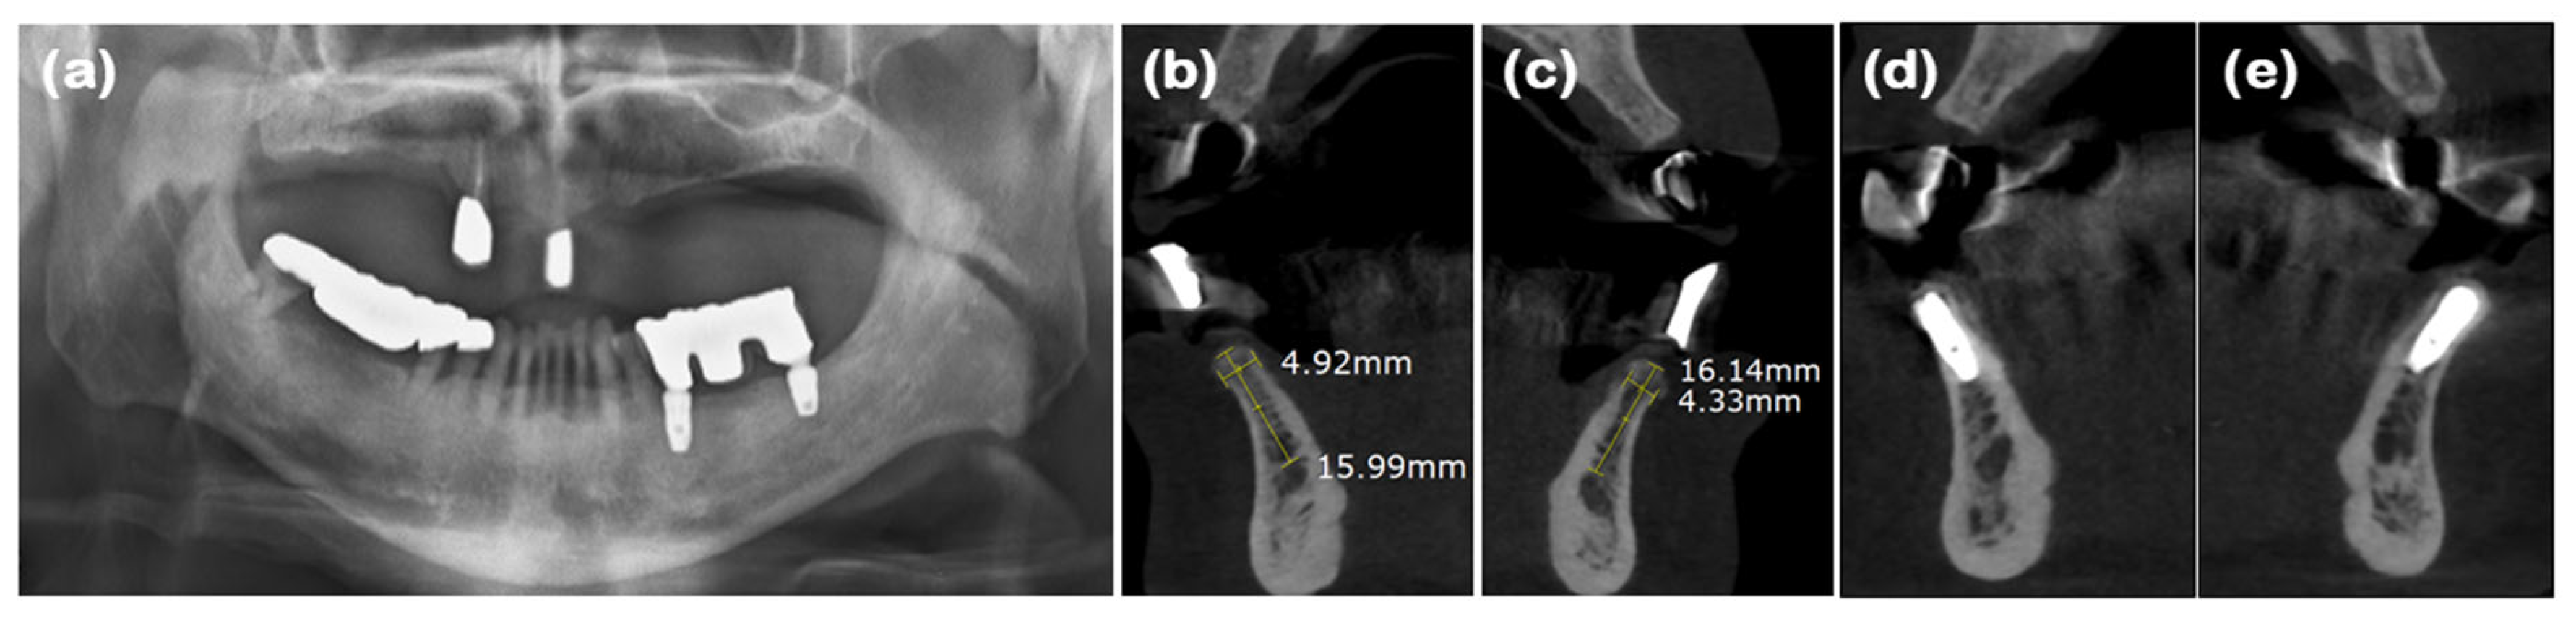

| Case 1 | Case 2 | Case 3 | Case 4 | ||||

| Tooth position | #23 | #16 | #17 | #32 | #42 | #45 | #47 |

| Ridge width (mm) 1 | 5.93 | 8.66 | 8.90 | 4.92 | 4.33 | 7.90 | 5.58 |

| Keratinized mucosa width (mm) 2 | 4 | 6 | 6 | 4 | 4 | 3 | 3 |